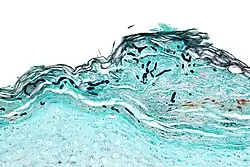

| Micrograph of a superficial dermatomycosis. The fungal organisms are the dark staining, thick, quasi-linear objects below with skin surface. Vulvar biopsy. GMS stain. | |